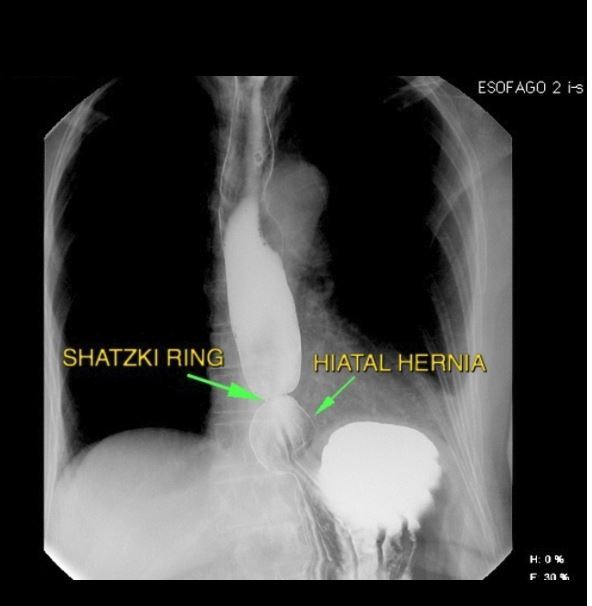

This is a Barium Swallow

Demonstrating... a dilated pouch (the hernia) below a smooth, short, symmetric, ring-like constriction (the GOJ) - Schatzki ring. May be assoc. c¯ smooth area of concentric narrowing in the distal oesophagus: reflux-stricture. I note (Significant negative) that there are no apple-core strictures seen

Hiatus Hernia